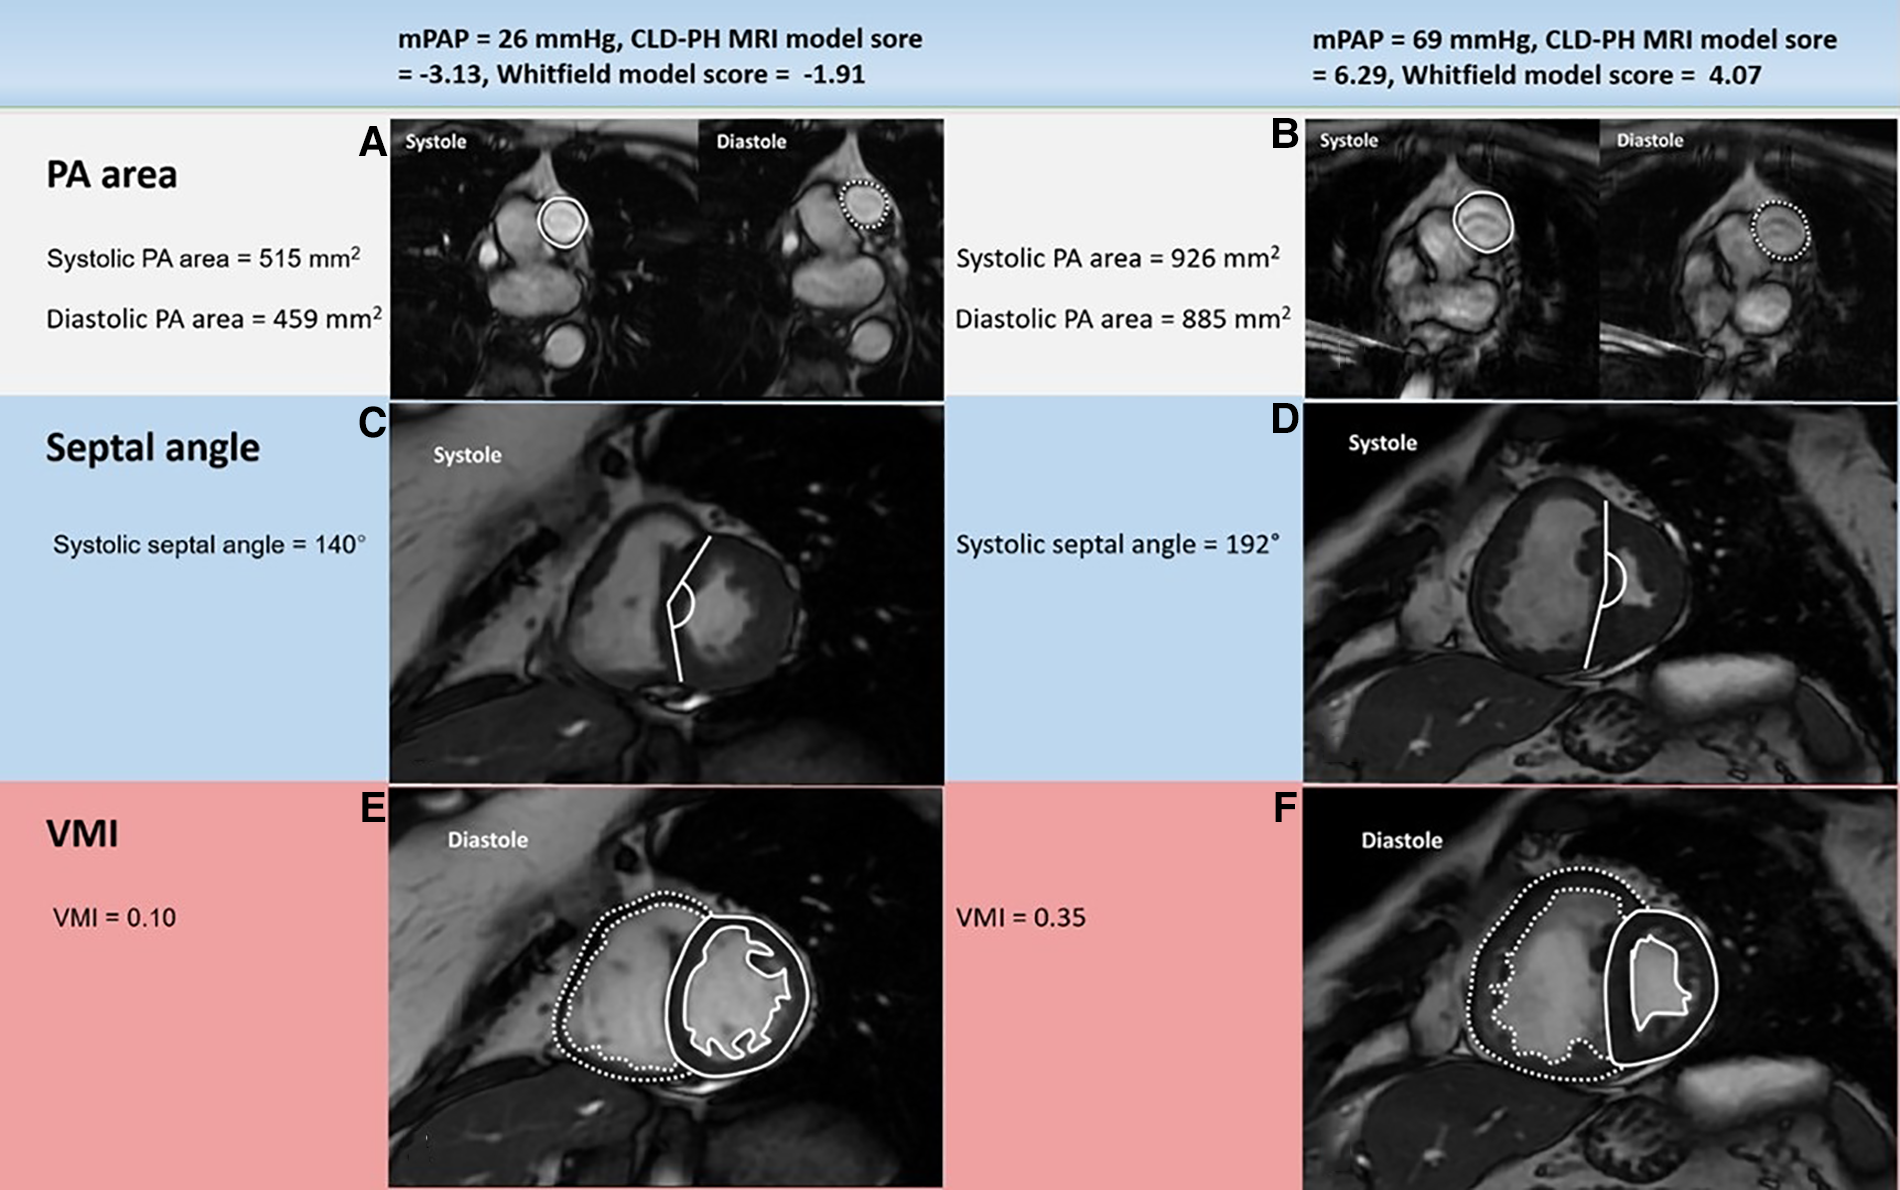

Example cardiac MRI images in patients with mPAP below (left) or above (right) 35 mmHg: PA area (A, B), systolic septal angle (C, D) and VMI (E, F). The patient with severe PH (right) had much larger systolic and diastolic PA areas, systolic septal curvature and VMI than the patient with mild-moderate PH (left). mPAP: mean pulmonary artery pressure; CLD: chronic lung disease; PH: pulmonary hypertension; PA: pulmonary artery; VMI: ventricular mass index; MRI: magnetic resonance imaging.

Image analysis was achieved using a GE Advantage Workstation 4.1 with the patient clinical information and the cardiac catheter data unavailable to the observer. Chambers trabeculations were included as part of the volume cavity measurement and were not separately traced (21). Right and left endocardial and epicardial surfaces were manually traced to obtain right ventricular end diastolic volume (RVEDV) and end systolic volume (RVESV), and left ventricular end diastolic volume (LVEDV) and end systolic volume (LVESV). Right ventricular ejection fraction (RVEF), left ventricular ejection fraction (LVEF), right ventricular stroke volume (RVSV) and left ventricular stroke volume (LVSV) were obtained using the end-diastolic and end-systolic volumes (20, 22, 23). These measurements were indexed for the body surface area and then corrected for age and sex and displayed as percentage predicted except RVEF and LVEF (24). SV was considered to be the most accurate from LV volumetry and was used to estimate RV-PA coupling and we have used the LV volumetry for SV rather than flow through PA/aorta as some studies proved the inaccuracy of the latter method and preferred the former method (25). Septal angle was measured as the angle of the septum from the RV insertion points to the centre of the mid septum (26). The interventricular septum was considered as part of the left ventricle for calculating the ventricular mass (Figure 2). RV end-diastolic mass (RV mass) and LV end-diastolic mass (LV mass) were derived. Ventricular mass index (VMI) was considered as the RV mass divided by the LV mass (27). Pulmonary artery (PA) areas were measured maximally and minimally and the following equation was used to calculate the relative area change: relative area change = (maximum area- minimum area)/minimum area (20). The well-established biplane area length method was used to measure the LA volume (28, 29).